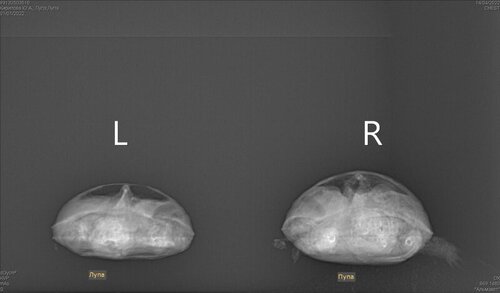

Mister.G Ваше имя: Глеб Локация: Россия, Барнаул Опубликовано: 14 апреля 2022 Автор Опубликовано: 14 апреля 2022 (изменено) @mothзаключение рентгенолога. Лупа это неактивный, а пупа активнее. Изменено 14 апреля 2022 пользователем Mister.G

Mister.G Ваше имя: Глеб Локация: Россия, Барнаул Опубликовано: 14 апреля 2022 Автор Опубликовано: 14 апреля 2022 @moth L- Это лупа, поменьше и не такой активный, R- Это пупа, побольше и чуть чуть поактивней